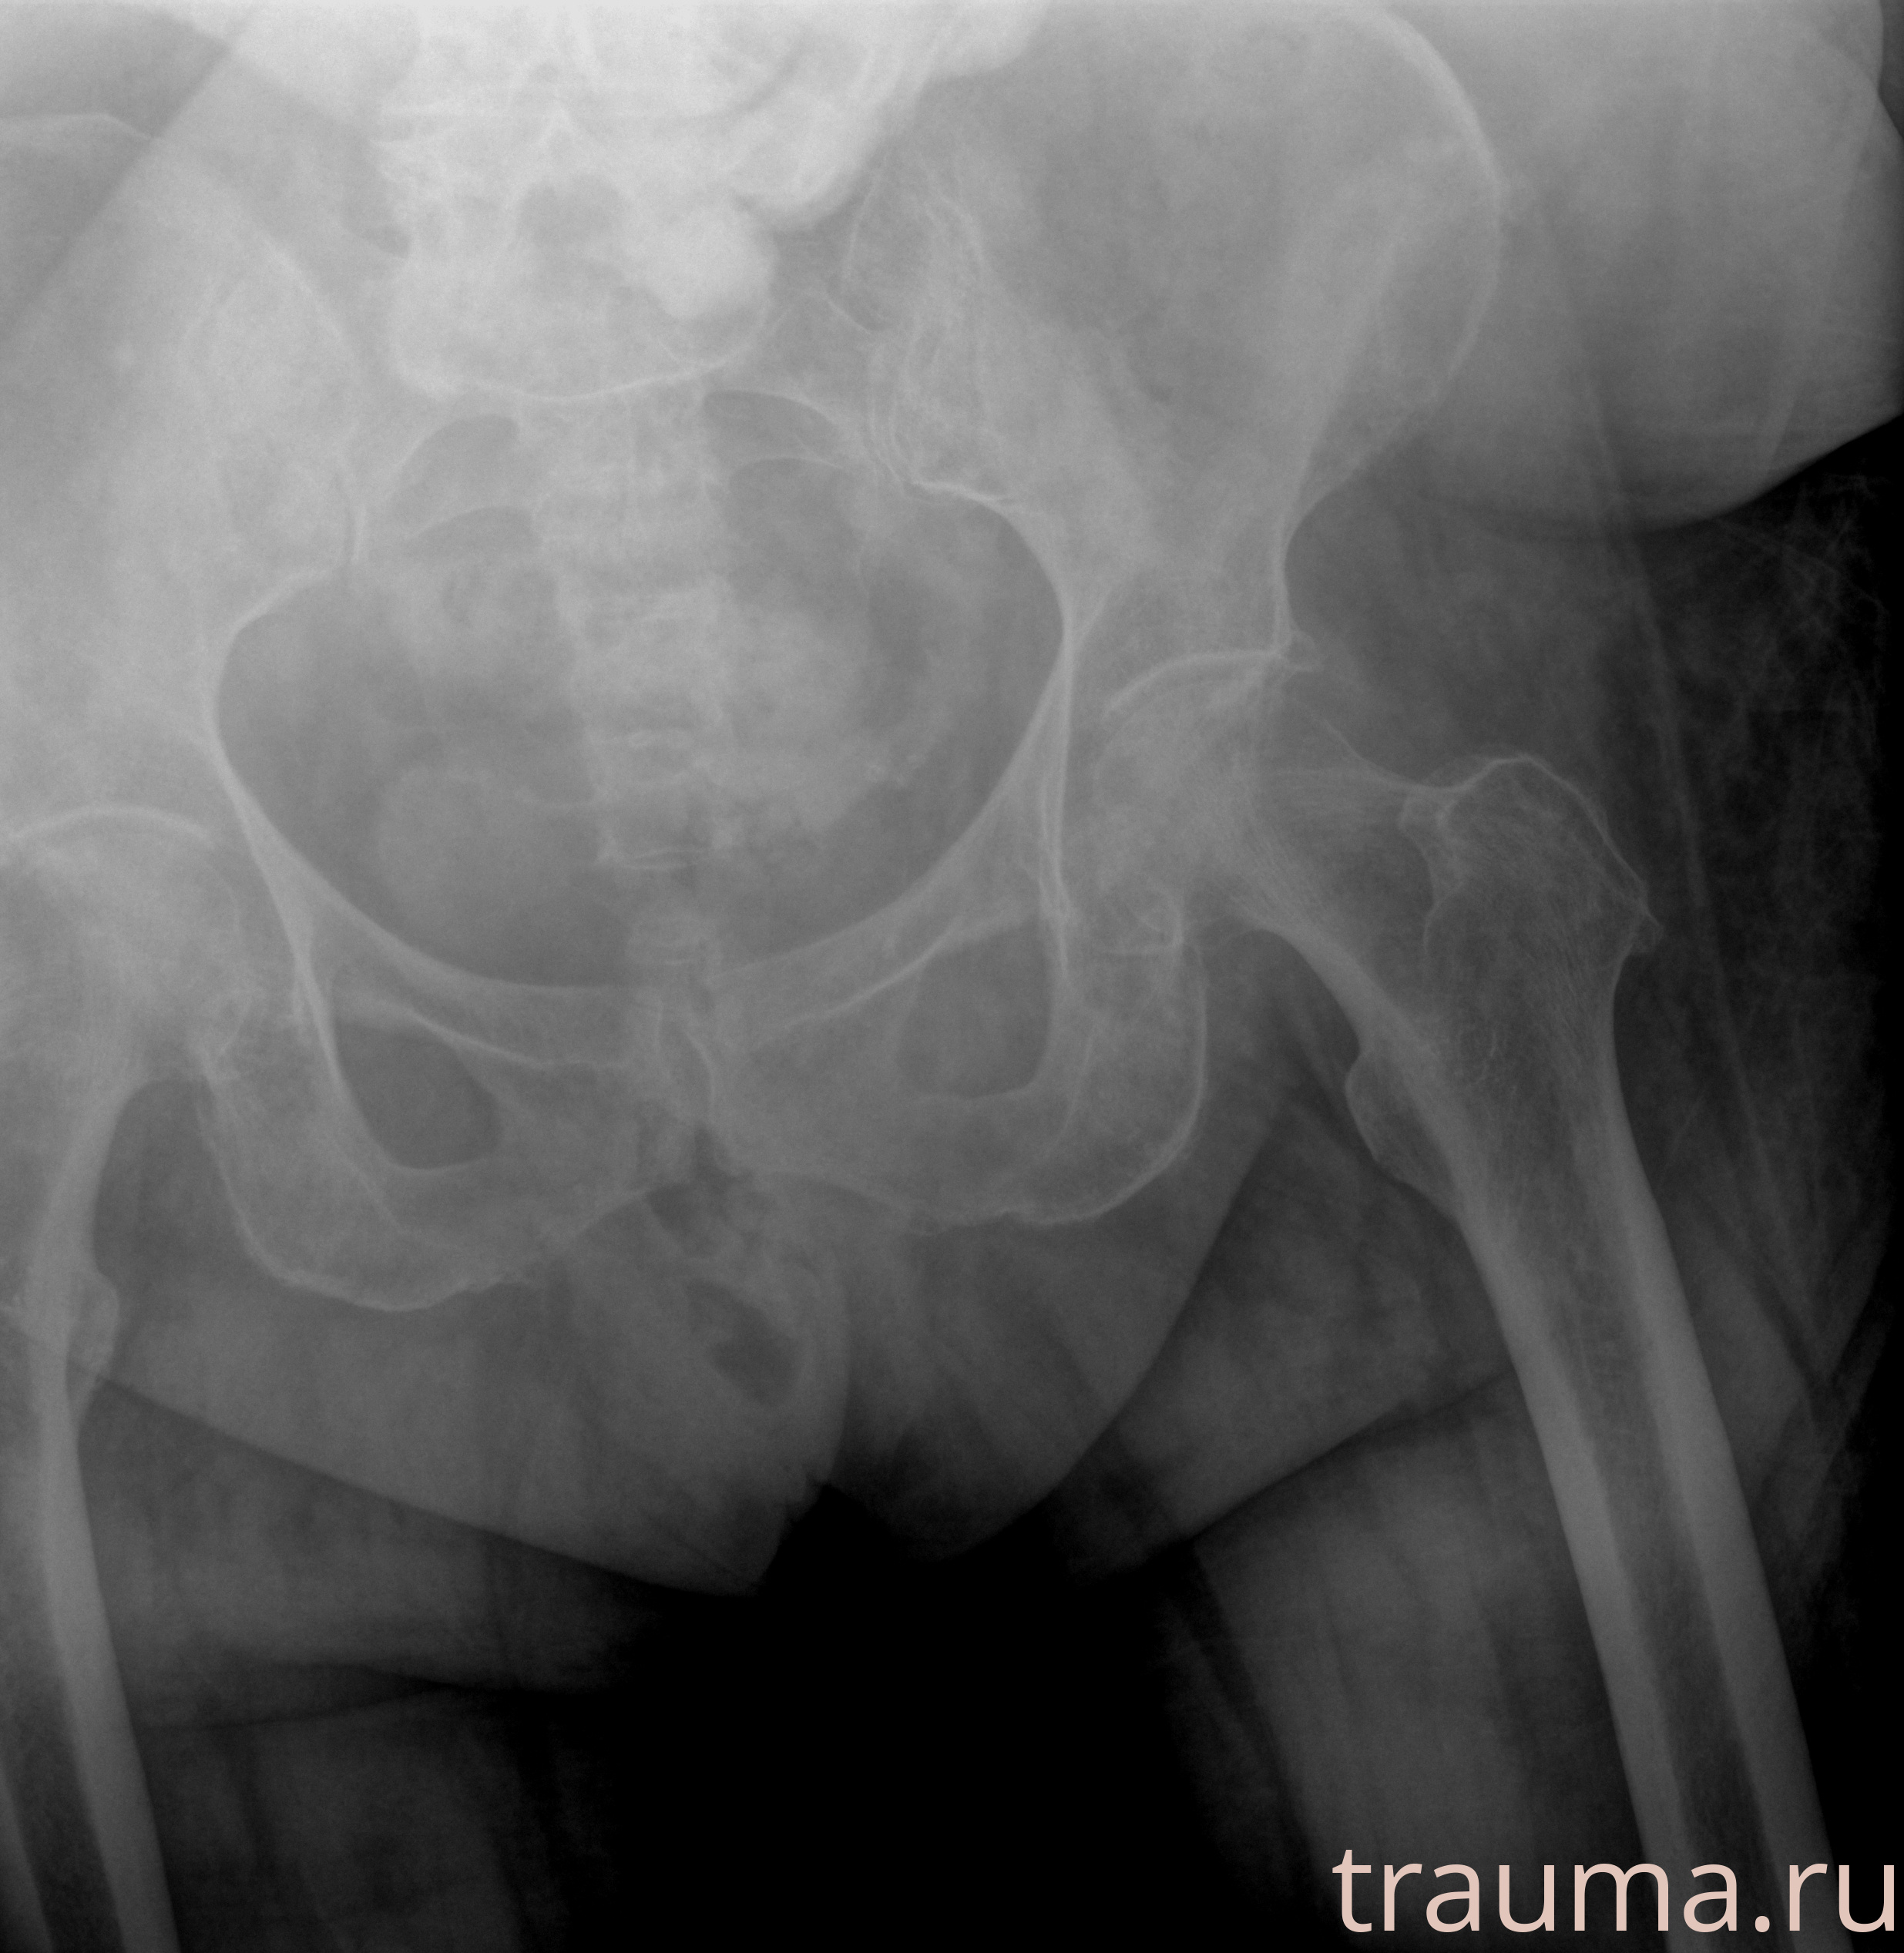

Рентген на дому: по вашему адресу приезжает врач-рентгенолог, травматолог-ортопед с мобильным рентгеновским аппаратом, проводит диагностику травмы или заболевания, делает необходимые рентгенограммы, дает рекомендации по дальнейшему лечению. Получить качественные снимки в домашних условиях возможно благодаря уникальной методике, разработанной МосРентген Центром для института  Склифосовского

при переломе шейки бедра и пневмонии от компании МосРентген Центр - партнера Института имени Склифосовского